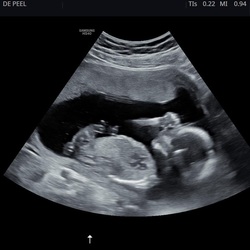

Ik ben zaterdag 24 weken en wij weten dat ons zoontje een complexe hartafwijking heeft. We hebben uiteindelijk na de 20 weken echo de nipt laten doen alsnog en beperkt genetisch onderzoek laten uitvoeren. Daar is niks uitgekomen maar het is nog niet uitgesloten dat hij niks anders heeft.

Dus wel andere situatie als jullie. We zijn benieuwd wat ons te wachten staat. Onze oudste heeft 3 maanden in het ziekenhuis gelegen na de geboorte en we weten nu ook niet zo goed waar we ons op voor moeten bereiden. We gaan het zien

Wij hebben in sept een dochtertje gekregen, met de 20 weken echo zagen ze ook dat de stand van het hartje niet juist was en dat er afwijkingen waren aan haar kleine hersentjes.

Wij hebben een punctie laten doen en daar kwam ook uit dat ze een deletie en duplicatie op chromosoom 12 heeft.